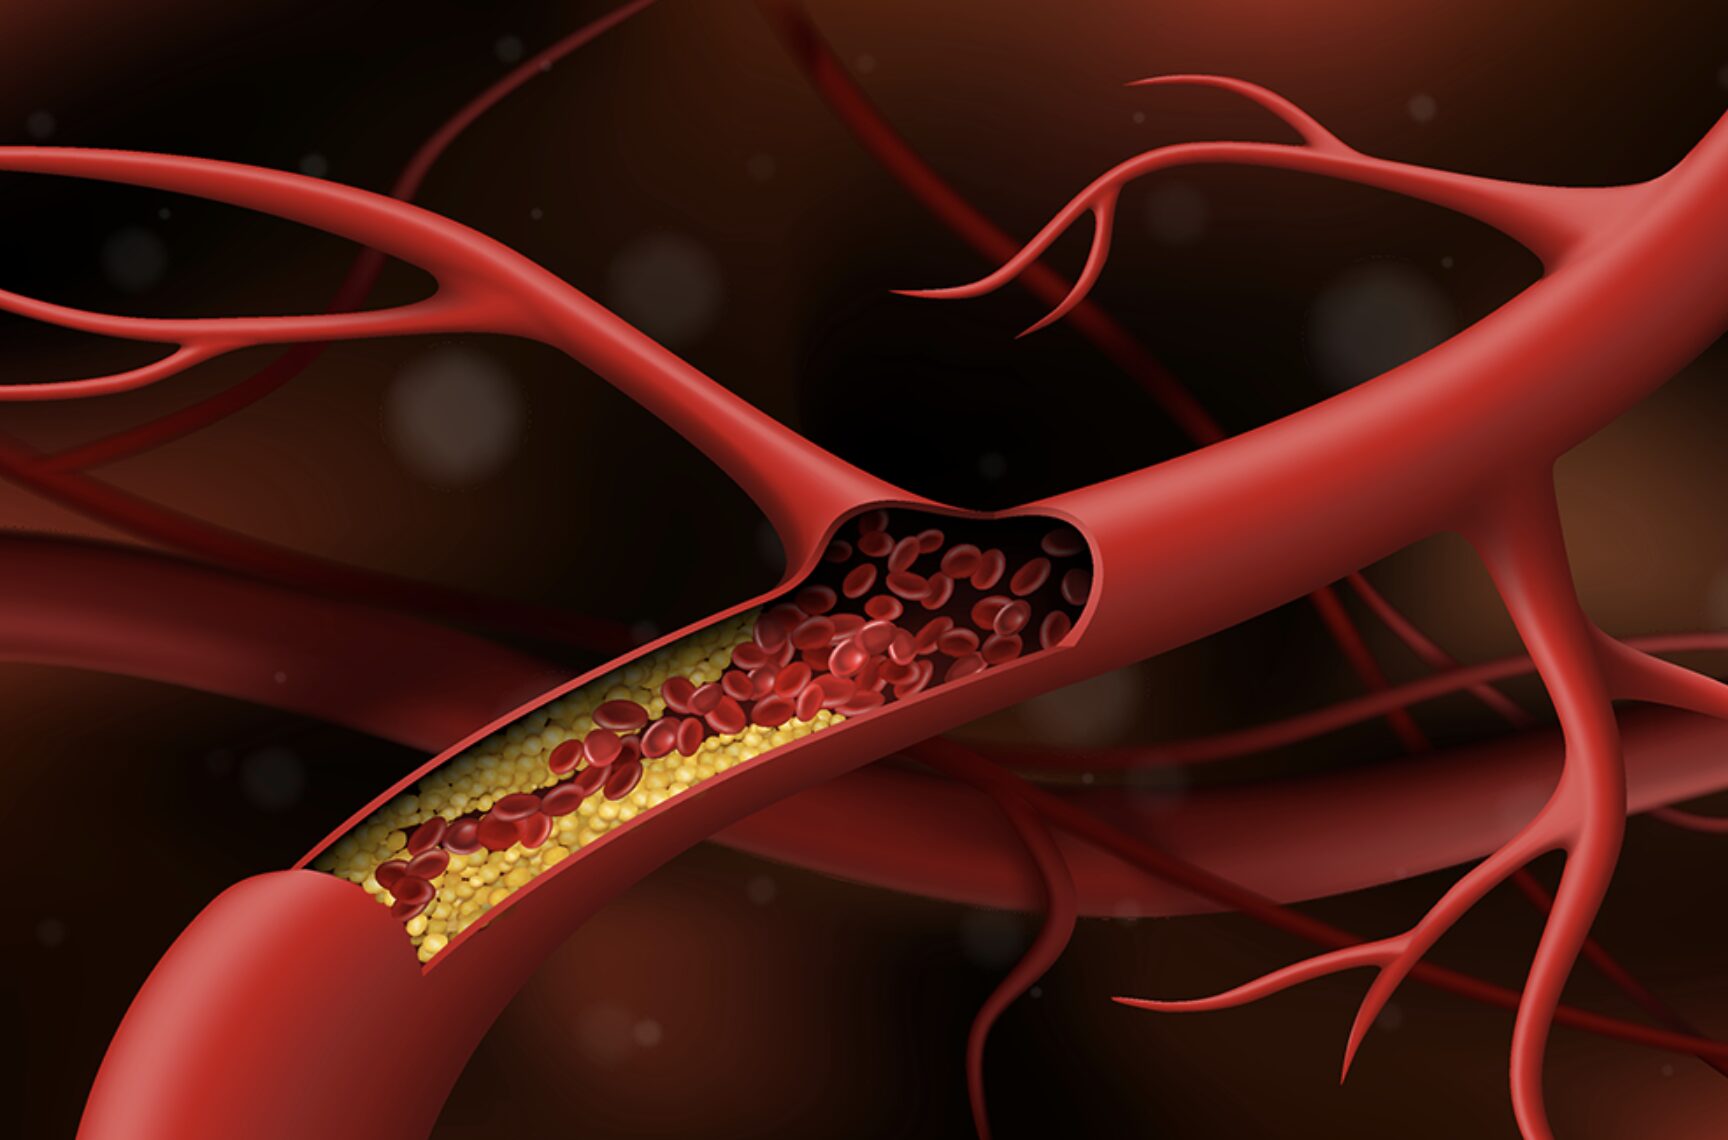

Nghiên cứu mới về “thời gian vàng” trong cấp cứu đột quỵ

Thông thường, các bác sĩ nghĩ rằng họ chỉ có 6 giờ để giải quyết cục máu đông trước khi xảy ra tổn thương não lớn. Tuy nhiên, hai nghiên cứu mới cho thấy họ có từ 16 đến 24 giờ để điều trị.